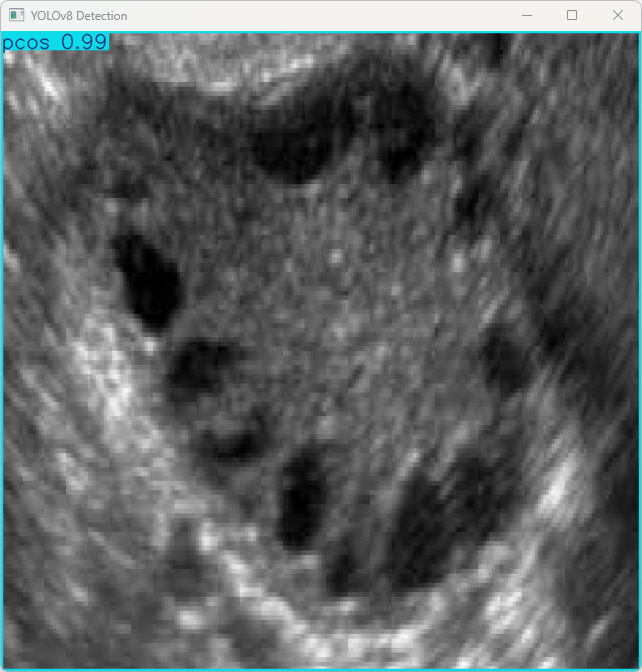

(1)res = results[0].plot():将检测到的结果绘制在图片上。

(2)cv2.imshow(“YOLOv8 Detection”, res):使用OpenCV显示检测后的图片,窗口标题为“YOLOv8 Detection”。

(3)cv2.waitKey(0):等待用户按键关闭显示窗口

执行imgTest.py代码后,会将执行的结果直接标注在图片上,结果如下:

这段输出是基于YOLOv8模型对图片“imagetest.jpg”进行检测的结果,具体内容如下:

图像信息:

(1)处理的图像路径为:TestFiles/imagetest.jpg。

(2)图像尺寸为640×640像素。

检测结果:

(1)1个PCOS对象,多囊卵巢综合症。

处理速度:

(1)预处理时间: 4.2 毫秒

(2)推理时间: 6.5 毫秒

(3)后处理时间: 102.1 毫秒

总结:

模型在推理时的表现非常好,检测出了PCOS,且推理过程非常快速,适合实时监控与检测。